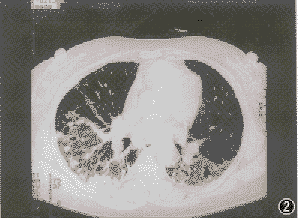

間質性肺炎影像圖 2.體徵 呼吸急促、發紺、雙肺中下部可聞及Velcro 囉音(連續、高調的爆裂音)有杵狀指趾,其中Velcro 囉音最具特徵性。

病變主要在支氣管、細支氣管和血管周圍,以及小葉間隔的結締組織內。X射線檢查可見纖細的不規則條紋狀密度增深影,自肺門向外伸展,邊緣較清晰,交織成網狀,有的局限於單側肺葉,多見於肺底。在網狀陰影間,可見分布不均勻的小點狀影。

間質性肺炎X線檢查 實驗室檢查:血液檢查:間質性肺病肺泡結構中炎性和免疫細胞異常與肺外其他病變無關聯,許多患者血沉增速,或血液免疫球蛋白增高,與肺纖維化亦無密切關聯。有些患者血清中可查到免疫複合體,是從肺臟產生而溢出的。有一部分患者類風濕因子、抗核抗體陽性,部分患者血清出現抗肺膠原抗體。動脈血氣分析:由於潮氣量減低,呼吸頻率增高,呼吸淺速,肺泡通氣量不足,導致通氣/血流比例降低,發生低氧血症,但動脈血二氧化碳分壓正常。運動後血氧分壓明顯下降。支氣管肺泡灌注檢查:套用纖維支氣管鏡插入左肺舌葉或右肺中葉,以生理鹽水沖入灌洗,獲得支氣管肺泡灌洗液。將灌洗液作細胞學和非細胞成分的測定。本法具有以下優點:①灌洗液的細胞學檢查能真實地反映肺泡炎肺泡結構中的炎性和效應細胞的類型與數目。②各種間質性肺病的診斷與鑑別診斷。非吸菸人灌洗液的細胞總數為(0.2~0.5)×10E4/ml 其中肺泡巨噬細胞占85%~90%,淋巴細胞約占10%,中性粒細胞及嗜酸粒細胞僅占1%以下,細胞總數多由肺泡巨噬細胞的增加而增加,而細胞種類的變化在ILD 時有診斷意義。如過敏性肺泡炎、結節病、慢性鈹肺時淋巴細胞顯示明顯增加。膠原病伴肺間質纖維化時也可見淋巴細胞增加。而細菌性肺炎、氣道感染以及ARDS 時嗜中性粒細胞增加。閉塞性細支氣管炎伴機化性肺炎時可出現淋巴細胞、粒細胞的增加。支氣管肺泡灌洗液的淋巴細胞中T 細胞占70%~80%,B 細胞占10%~20%,而ILD 中的結節病、過敏性肺泡炎、慢性鈹肺則T 細胞增加。一直想用標記T 細胞亞群或T 細胞、B細胞的活化程度解釋ILD 的活動性和預後。僅見結節病時T細胞數及活化T 細胞數的增加與病情的進展情況相關。此外在特發性肺間質纖維化時活化的B 細胞增加則提示病情的進展,淋巴細胞增多則對激素治療效果較好,其預後也較好。

間質性肺炎確診圖 2.肺功能檢查 此項檢查僅是功能的診斷,而非病理診斷,在早期階段,肺功能檢查可以完全正常,當病情進展才可能出現肺功能檢查的異常。ILD 最顯著的肺功能變化為通氣功能的異常和氣體交換功能的降低。通氣功能是以限制性通氣障礙為主、肺活量減少、殘氣量隨病情進展而減少,隨之肺總量也減少。第1s 時間肺活量(FEV1.0)與用力肺活量(FVC)之比即1s 率出現明顯升高,如已達到90%則支持ILD 的診斷。ILD 的早期可有小氣道功能障礙,其V50、V25均降低ILD形成纖維化後而出現V50、V25 增加。ILD 的早期還可以出現氣體交換功能障礙,如彌散功能(DLCO)較早期即有降低,一旦X 線胸片發現間質性改變,DLCO 則已降低50%以下。肺功能改變與肺部病變二者的相關性,在病變輕微者極差,病情嚴重者相關性較好。凡肺功能嚴重損害者,肺部病變肯定嚴重。在肺功能的各項檢測中,容量-壓力曲線測驗和運動時動脈血氧的變化,僅在反映肺纖維化的嚴重程度上最為敏感。肺功能檢查對於ILD 的早期診斷與判定預後是非常有用的,特別是動態觀察VC、FEV1.0、DLCO 等指標。至於肺功能檢查能否判斷激素或免疫抑制劑治療ILD 的療效,有不同的看法,僅以肺功能的變化評價療效是不夠的。